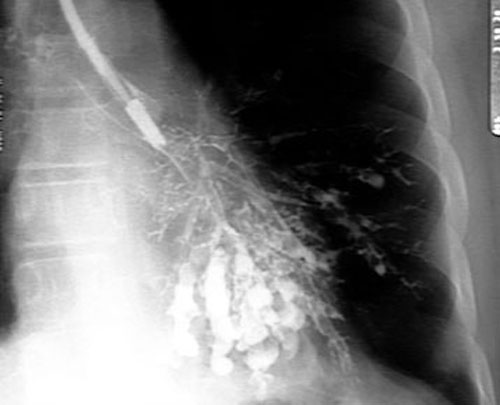

Фотографии и информация о бронхоскопии при туберкулезе